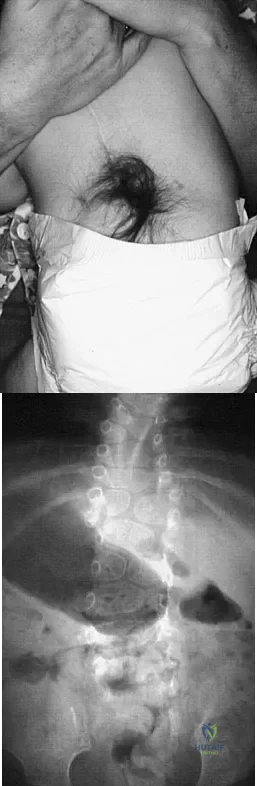

Question 35

A 4-month-old infant is referred for evaluation of congenital scoliosis. The child has no congenital heart anomalies, and a renal ultrasound shows that he has one kidney. Examination reveals mild scoliosis and a large hairy patch on the child's back. Neurologic evaluation is normal for his age. A clinical photograph and radiograph are shown in Figures 19a and 19b. Initial management should consist of

Explanation